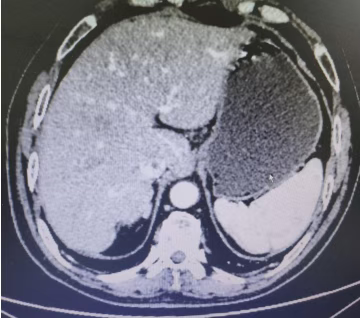

Abdominal CT films (2 sheets) on February 23, 2023

The patient was diagnosed with advanced gastric cancer. Through standardized chemotherapy, good compliance, and an optimistic attitude, their survival period has exceeded 5 years. Currently, their physical condition is favorable, and they have achieved clinical cure of the tumor—far exceeding the expectations of both the medical team and the patient.